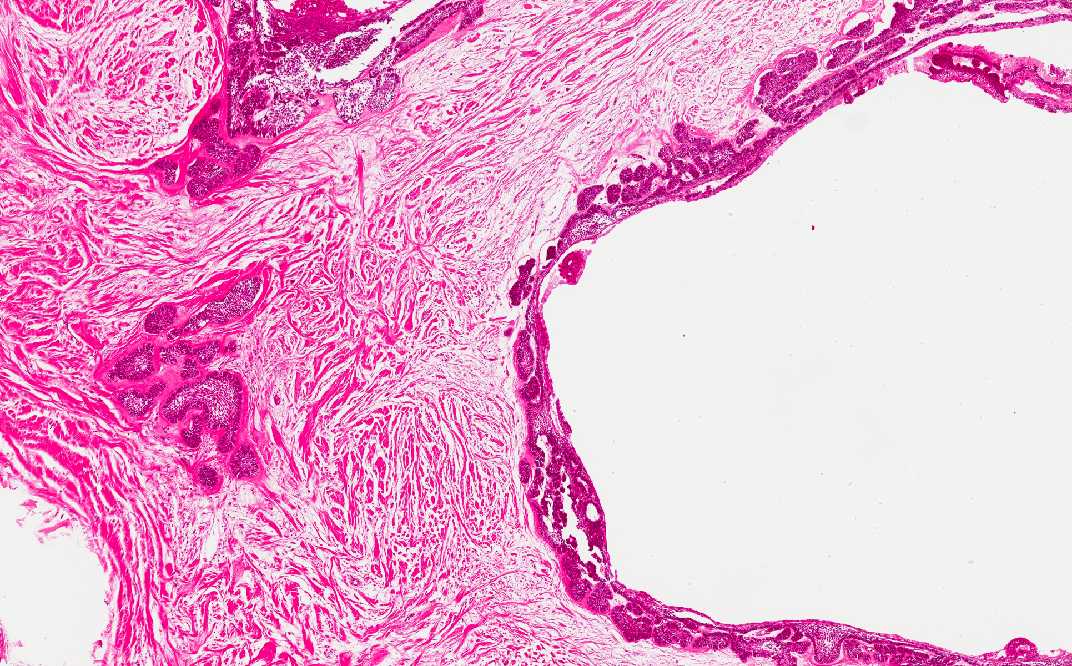

Area 2: Note that the cyst are lined by palisading columnar cells with reversed polarity. Cyst formation is very common in ameloblastomas. Some of the cyst may be, at least partially, lined by attenuated squamous epithelium that lacks features of ameloblasts.

Histologic Highlights of this Case:

• In Area 2, cyst formation is present. The cysts are lined by the cells with pseudopalisading pattern similar to that of area 1.

• The overall nuclear features are bland and without significant pleomorphism or high grade atypia. Mitotic figures are not readily seen.

• Note that the specimen appears more eosinophilic than other specimens being shown in this program. This is because the specimen has to be decalcified before examination and slightly over decalcified specimens often appear more eosinophilic and the nuclear details are not as well preserved.

• The histologic appearance is also characteristic. Recurrence is common. There are islets or plexiform arrangement of epithelial cells.  The cells resemble the enamel organ of the developing tooth germ. Typically the epithelial islets consist a peripheral layer of cuboidal or columnar cells which may be rather like ameloblasts and a central area of cells similar to stellate reticulum.